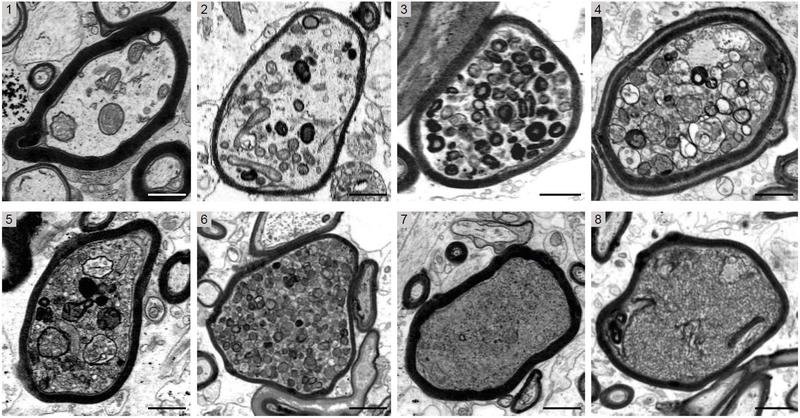

„Wenn Oligodendrozyten einer akuten entzündlichen Umgebung ausgesetzt sind, könnten sie ihre unterstützende Funktion für die Nervenfasern verlieren und das Myelin wird zu einer Bedrohung für das Überleben der Nervenfasern“, beschreibt Prof. Klaus-Armin Nave vom Max-Planck-Institut für multidisziplinäre Naturwissenschaften in Göttingen die eingangs aufgestellte Forschungshypothese des Teams. Um ihre Vermutung zu überprüfen, untersuchten die Forschenden Gewebeproben von Patient:innen mit Multipler Sklerose und zusätzlich verschiedene Mausmodelle dieser Krankheit, um den Autoimmunangriff auf das Myelin experimentell nachzustellen. Dabei konnten sie erstmals in den Gewebeproben der Erkrankten mit Elektronenmikroskopie nachweisen, dass die irreversible Schädigung fast immer in den noch mit Myelin ummantelten Axonen auftritt (s. Abbildung). Umgekehrt konnten die Wissenschaftler:innen mit Hilfe von genetisch veränderten Mausmodellen zeigen, dass „nackte“ Axone in einer akuten entzündlichen Region des zentralen Nervensystems besser vor der Degeneration geschützt sind.